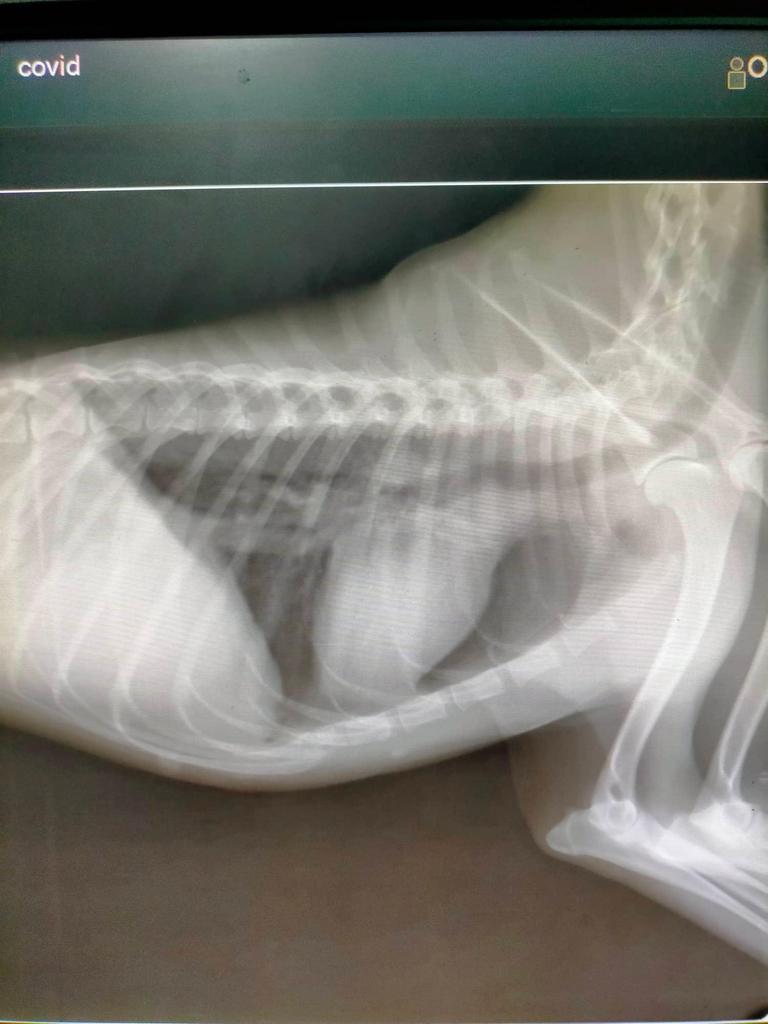

There is no doubt that the tumor needs to be removed. Although Kai was tested negative for distemper, he is positive for ehrlichia. He has high infection, anemia, and a moderately low platelet count. He has possible pancreatitis and is very very stressed - probably also due to severe tumor. He also has an infection of his burdened liver.

Most of these things are caused by the very existence of the tumor, hence the need for very urgent and expensive surgery. Of course complications may arise, we cannot rule this out... But the tumor will only grow bigger and more painful.

Kai suffers from pulmonary opacification. This condition needs to be treated firstly, before he can undergo the surgery. These costs cannot be afforded by owners as well.